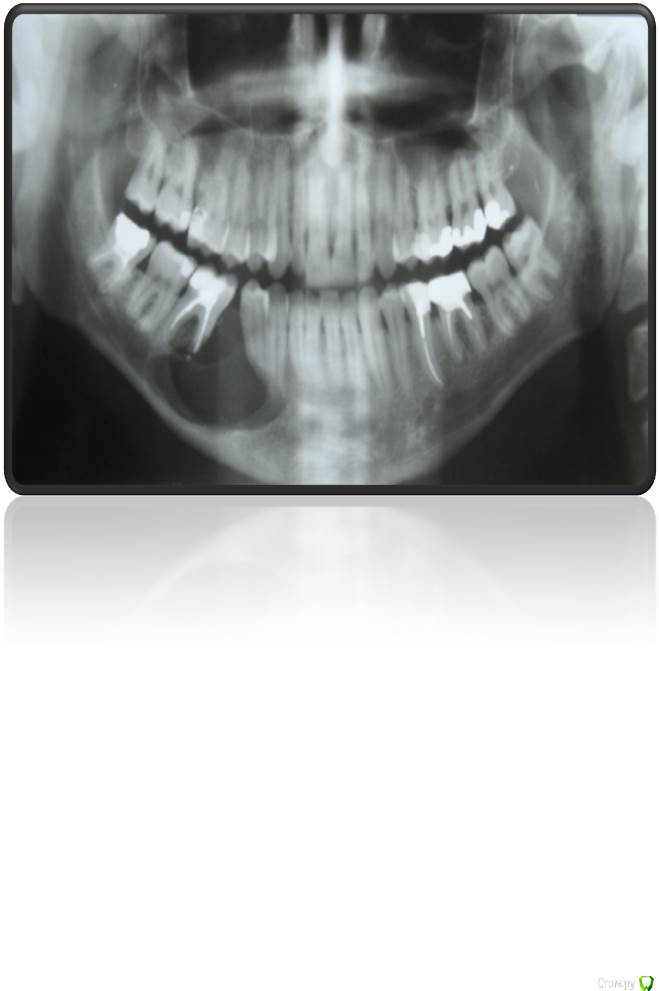

natan. Опубликовано 21 мая, 2015 Поделиться Опубликовано 21 мая, 2015 пациенту 30 лет,здоров.пришёл с букальной припулостью справа. Ссылка на комментарий

Astronaft Опубликовано 22 мая, 2015 Поделиться Опубликовано 22 мая, 2015 Очаг разрежения находится над каналом -> вероятная одонтогенная природа. Края не рваные, ровные, раздвигает зубы - гидравлический рост. 1.Одонтогенная кератокиста2. латеральная периодонтальная киста3. радикулярная киста Ссылка на комментарий

natan. Опубликовано 23 мая, 2015 Автор Поделиться Опубликовано 23 мая, 2015 Ameloblastoma mural type Ссылка на комментарий

natan. Опубликовано 24 мая, 2015 Автор Поделиться Опубликовано 24 мая, 2015 амелобластома отн-ся к группе одонтогенных опухолей.не буду останавливаться на их видах ,в данном случае диагноз unicystic ameloblastoma mural type что требует аггрессивного лечения т.е.резекция в пределах здоровых тканей.На самом деле на тему амелобластом можно говорить неограниченое время т.к. интересна своими видами и разными подходами лечения .В этом случае на 1-м этапе выполнили сегмент.резекцию и поставили reconstraction plate,на 2-м этапе free fibula (пластическими хирургами) и дальше имплантация. 3 Ссылка на комментарий